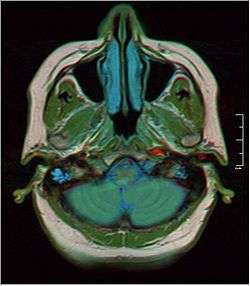

Horizontal section through left ear; upper half of section.

Mastoid cells.- Lateral head anatomy detail.Facial nerve dissection.